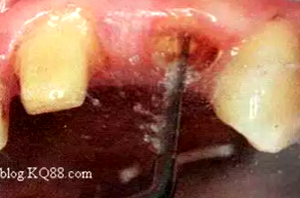

2. 清除根管壁殘留物

根管壁殘留物的存在直接影響纖維樁的粘接和固位,這也是導(dǎo)致纖維樁脫落的主要原因。

(根管內(nèi)殘留物)

個(gè)人見解:必要的情況下先開闊根管口建立一定的視角后,慢速手機(jī)上G鉆為引導(dǎo)鉆,由號(hào)遞增引導(dǎo)開闊通路;P鉆預(yù)備樁道,同樣需要由小向大號(hào)遞增,直到選擇好適合的號(hào)預(yù)備到規(guī)定測(cè)量的深度即可,再配合纖維樁系統(tǒng)中各型號(hào)纖維樁所匹配的樁道鉆,預(yù)備、修整成與纖維樁相適應(yīng)的樁道。

預(yù)備后根管壁上會(huì)不同程度的牙膠和封閉劑等殘留物,所以樁道預(yù)備前后建議X線片輔助檢查預(yù)備深度等情況,而殘留物也會(huì)很清晰地顯現(xiàn)。